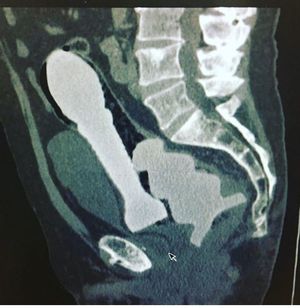

Ok so a not so glamorous part of my job is removing “foreign bodies” from various parts of the human body. This is a CT scan (not mine) of not one but two toys impacted into the rectum😳😳😳                          Source; Dr Buck Parker

Sliding into Monday late to work like.... Ok so a not so glamorous part of my job is removing “foreign bodies” from various parts of the human body. This is a CT scan (not mine) of not one but two toys impacted into the rectum😳😳😳 Source; Dr Buck Parker